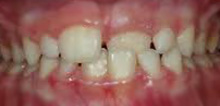

Einige Fehlentwicklungen des Gebisses sollten durch frühes Eingreifen im Milchgebiss unterbrochen werden. Diese frühe Weichenstellung kann später viel kompliziertere Behandlungen überflüssig machen. Das gilt vor allem für Kreuzbisse und große Abweichungen zwischen Ober- und Unterkieferlänge. Frühbehandlung heißt aber auch Einfluss auf ungünstige Angewohnheiten wie Daumenlutschen, Wangenbeißen, falsches Schlucken, eine falsche Zungenruhelage etc. zu nehmen. Solche Gewohnheiten können sonst zu Deformationen der Kiefer führen, die sich mit dem Durchbruch der neuen Zähne auch auf das bleibende Gebiss und dessen gesamte Funktion übertragen.

Festsitzende Apparaturen

Bei bestimmten Zahnfehlstellungen sind nur mit festsitzenden Apparaturen optimale Ergebnisse möglich.